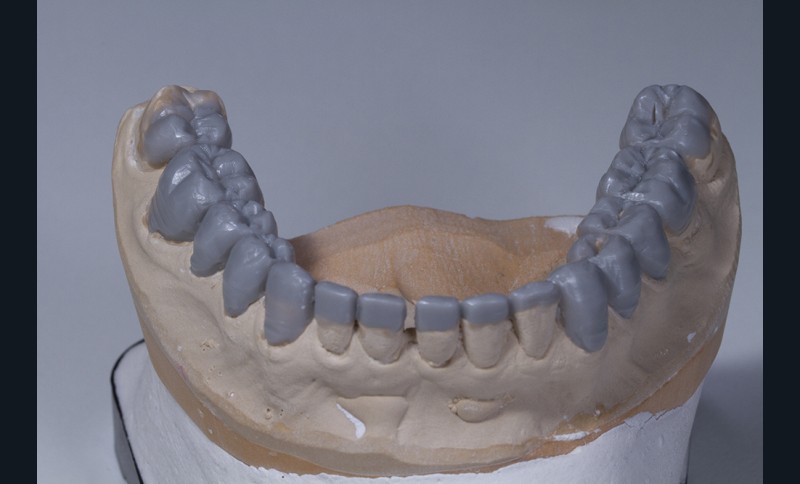

Le wax-up est préférentiellement élaboré en deux temps [17] : un wax-up dit esthétique, concernant uniquement les faces vestibulaires des dents de 15 à 25 puis un wax-up complet.

Dans un deuxième temps, un wax-up global permet de restaurer les courbes d’occlusion. Il est à noter que la présence d’égressions dentaires, faute d’antagoniste ou d’anciennes restaurations prothétiques inadaptées, crée des usures inégales au sein de la cavité buccale. Aussi, la présence de zones non recouvertes par le wax-up dans les secteurs postérieurs est courante, permettant ainsi la préservation de zones amélaires majeures pour le collage (fig. 2).

Le wax-up est le point de départ pour la réalisation de temporisations en technique d’isomoulage. Pour cela, le repositionnement de la clé en silicone s’effectue grâce à la réalisation de butées d’enfoncement sur des zones non waxées ou volontairement déwaxées (fig. 3).